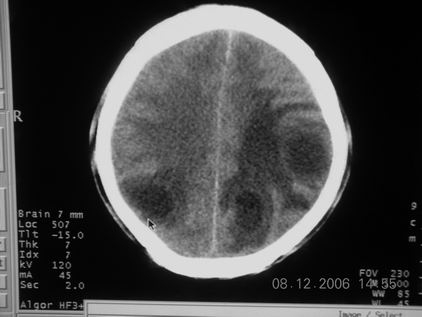

标题: CT11164:男,46岁,白血病患者,,大家看看. [打印本页]

标题: CT11164:男,46岁,白血病患者,,大家看看.

以前的片子,病史忘了,男,46岁,白血病患者,后来到中山二院诊断为

谁见过白血病中枢系统改变是怎么样的吗?

白血病脑浸润。

支持白血病脑浸润.

1 多发脑脓肿可能性大.>2 白血病浸润.

白血病脑浸润。没见过!但结合病史应首先考虑此病。

支持白血病脑浸润

结合病史考虑白血病脑浸润。

结合白血病病史,支持考虑白血病脑浸润。

结合病史考虑白血病脑浸润